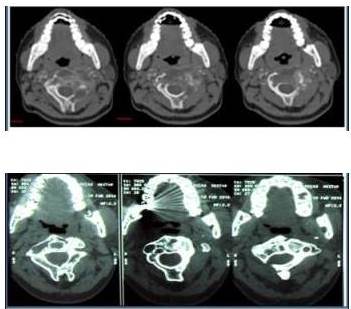

Se realiza simulación con máscara termoplástica inmovilizadora. Se planifica tratamiento con técnica de radioterapia conformada 3D, utilizando campos laterales opuestos y fotones de 6 MV dirigidos a la lesión a nivel de la cervical 2 (C2). Recibió una dosis total de 2 000 cGy, en dos semanas, con 10 fracciones diarias. Desde el 28/04/08 al 09/05/08. La tolerancia fue satisfactoria (Figura 1). El paciente ha evolucionado favorablemente en el último control de febrero 2014, la lesión en C2 se había reducido. En el último control clínico de abril de 2015 estaba asintomático, sin alteraciones al examen físico (Figura 2). Fue contactado por vía telefónica en agosto de 2018 y no refiere síntomas.

2008 antes de la radioterapia y 2014 después de la radioterapia